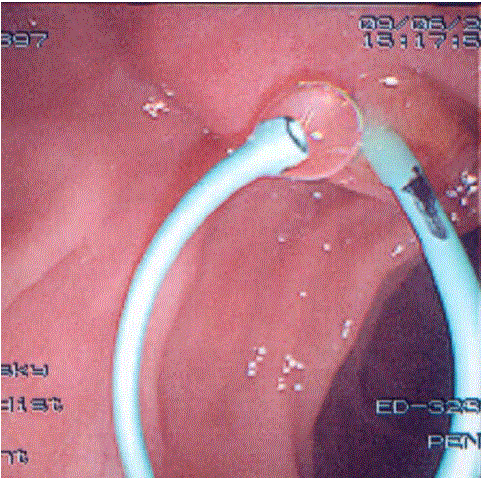

observed

Figure 10: Obvious drainage is observed from a 12 cm long 4 F single pigtail pancreatic stent placed in a patient following normal sphincter of Oddi manometry. The stent does not have proximal flaps to facilitate spontaneous distal migration.